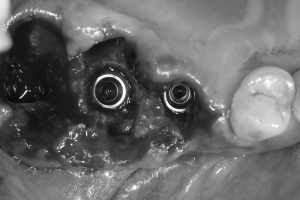

週明けの月曜日 本日は昼過ぎから、70代後半の方の上下インプラントオペ 患者さんは当クリニックにて、既に3本のインプラントが装着されてるインプラント経験者です。 美食家であり『煩わしい入れ歯は嫌だ!』と

左上6番は、秘密兵器デンサーバーを使い、自家骨とコラーゲン製剤のみでの挙上。

3本共に埋入計測値も良く6週間後には仮歯に

今回は、患者さんが遠方にお住まいですので無理なくヒーリングアバットだけで終わりました